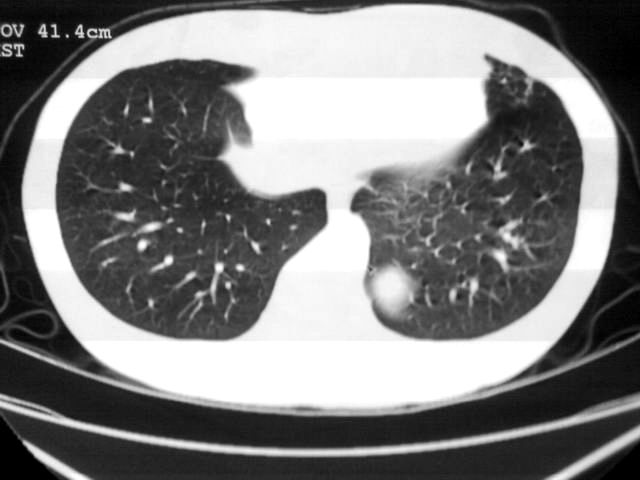

以下是引用苯小孩在2007-4-24 19:46:00的发言:[br]左下肺内侧基底段,见类圆形病灶,边缘清晰光滑.强化后轻中度强化.<平扫第4层面似有从腹主动脉相连血管影,可惜强化扫描这层没有抓住>考虑:左下肺隔离症.建议dsa或薄层强化重建观察.

以下是引用同在2007-4-24 20:11:00的发言:[br]考虑肺隔离症